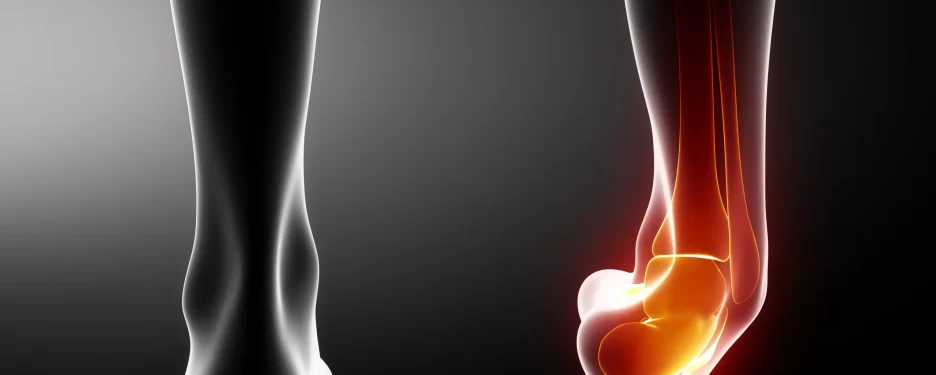

Ligament sprains - we've all been there! These pesky injuries can happen in any joint in your body, and boy, can they be a pain. But fear not, because we've got all the information you need to know about ligament sprains, and how to bounce back stronger than ever.

Now, let's break it down. Ligaments are the tough bands of tissue that connect your bones to each other. When these ligaments get stretched or torn, we've got ourselves a sprain. Ouch! But here's the thing, not all sprains are created equal. They come in different grades, from mild to severe.